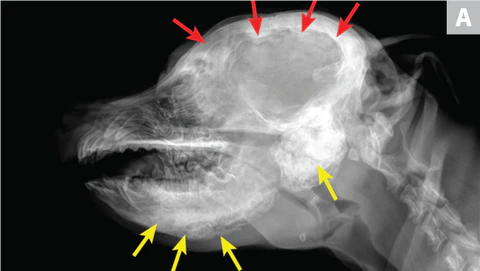

11. Craniomandibular Osteopathy

Craniomandibular osteopathy affects the lower jaw of dogs.

It can also affect the round bones behind the ears.

Some sections of the dog’s jawbones are replaced by immature bone.

Even though the cause is unknown, it is probably genetic because it affects growing Terriers more than other breeds.

Craniomandibular Osteopathy

Symptoms of craniomandibular osteopathy include mouth discomfort, pain, weight loss, and fever.

If your Terrier displays these signs, visit your vet to conduct X-rays to rule out this bone disorder.